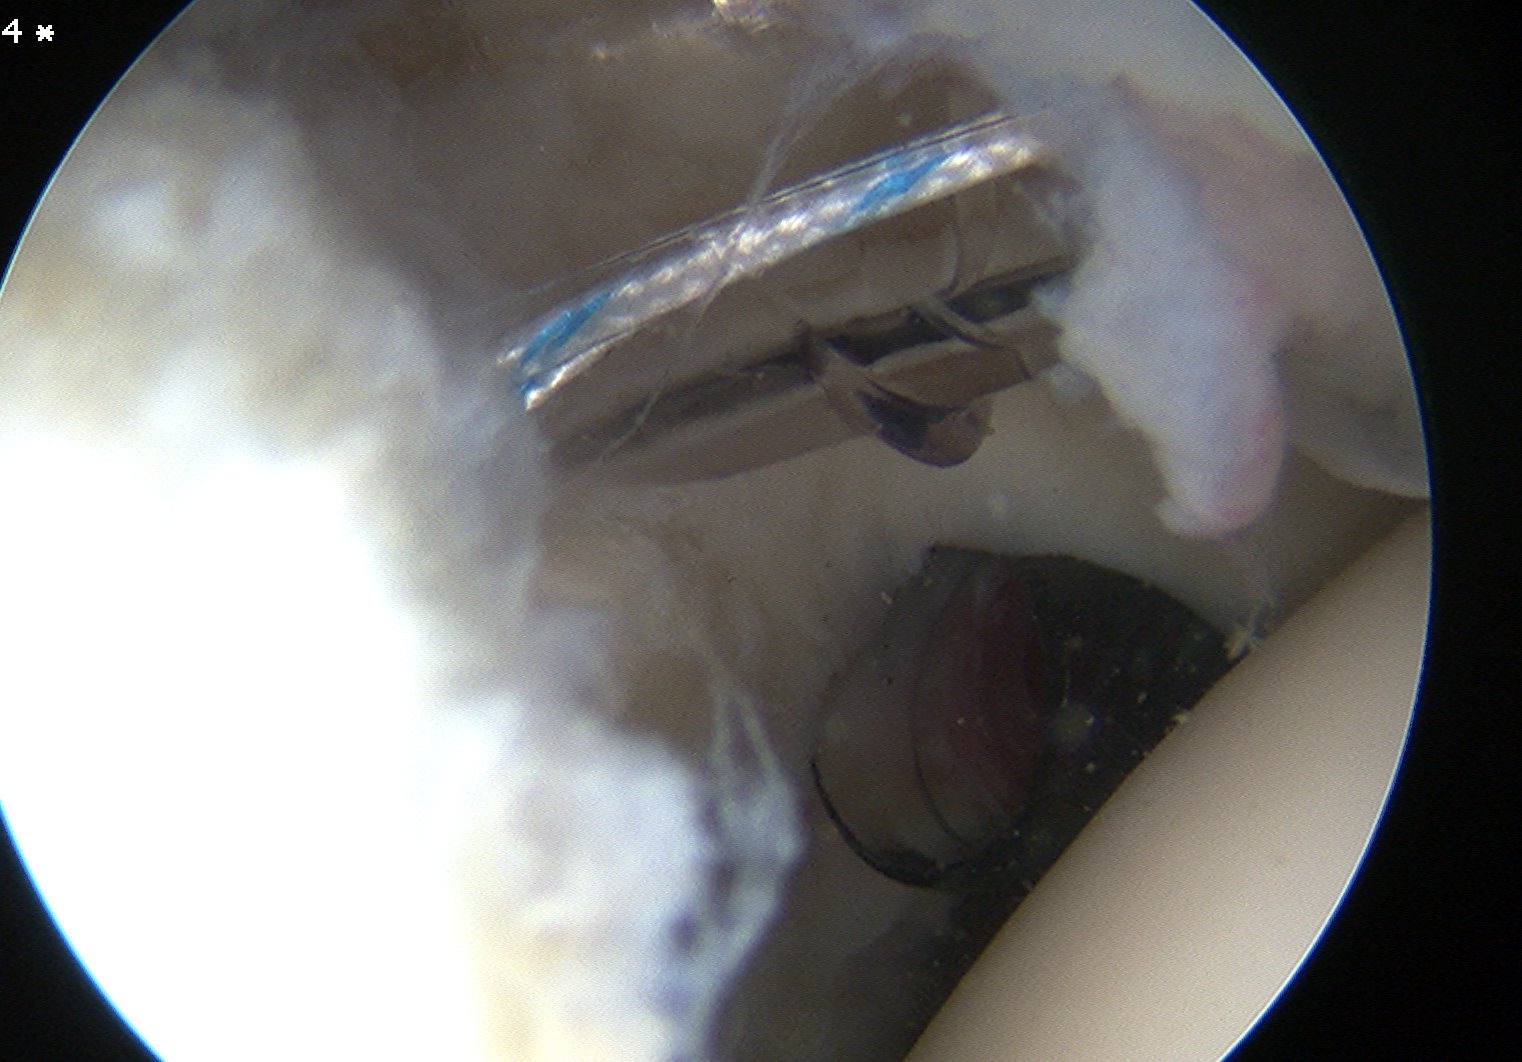

3. Anchors

Drill and insert via Wilminton portal

- insert anchor

- suture through each cannula

- limb through W portal will be the suture limb that is passed

- suture passer through anterior portal (right angled for left shoulder)